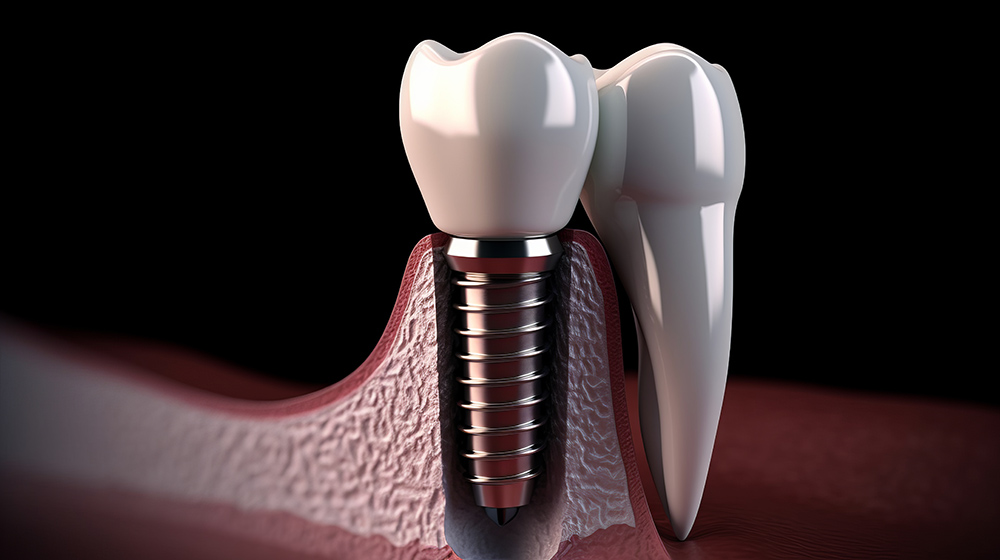

발치 후 임플란트 기간은 일반적으로 두 가지 방식으로 진행됩니다. 첫 번째 방식은 발치와 동시에 임플란트를 심는 즉시 임플란트 방식입니다. 이 방식은 시술 기간을 단축시키고, 환자의 불편함을 최소화하는 장점이 있습니다. 그러나 이는 충분한 뼈와 잇몸 상태를 요구하며, 모든 환자에게 적합하지는 않습니다.

두 번째 방식은 발치 후 일정 기간이 지난 후 임플란트를 심는 방식입니다. 이 경우, 발치 부위가 치유될 시간을 갖게 되어 감염의 위험을 줄일 수 있으며, 보다 안정적인 임플란트를 심을 수 있습니다. 일반적으로 발치 후 치유 기간은 2-3개월 정도 소요됩니다. 치유 과정 동안 뼈가 충분히 재생되어 임플란트의 성공률을 높이는 데 기여합니다.